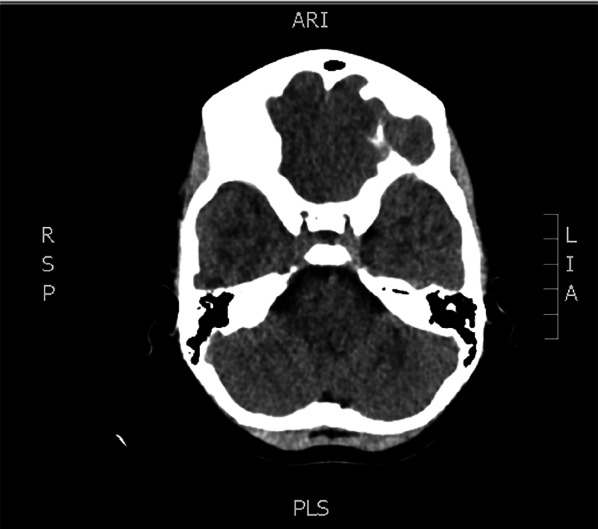

Ocular Point of Care Ultrasound (PoCUS) is emerging as a valuable utility within emergency medicine. Optic nerve sheath diameter (ONSD) has been demonstrated to correlate closely with intracranial pressure (ICP) and an elevated measurement can detect raised ICP readily, where fundoscopy may not, owing to both technical challenges and insufficient clinical skills. A previously fit and well 10-year-old girl presented to the paediatric emergency department with worsening headache, fever and lethargy. On examination, her left pupil was large, and not reactive to light. Initially, her GCS was 15 but suddenly dropped to 8/15. Her blood tests showed raised inflammatory markers. A CT head was reported as possible pansinusitis and MRI of her brain was initially reported as showing evidence of meningeal irritation only. Due to her drop in GCS PoCUS of optic nerve sheath was conducted which showed evidence of increased ICP with increased optic nerve sheath diameter of 6.8mm. This led to a reassessment of the MRI imaging by the neurosurgical team who felt there was evidence of subdural empyema. The patient was transferred to the tertiary neurosurgical centre, where an emergency evacuation of subdural empyema was carried out. Staphylococcus aureus and Streptococcus pyogenes were grown from pus samples. Early detection of raised ICP is of paramount importance in terms of being able to instigate neuroprotective measures and prevent adverse neurological outcomes. PoCUS is a readily available, non-irradiating, easily repeatable, well-tolerated and readily teachable ultrasound modality and a useful tool which should be employed in paediatric and adult emergency departments.

眼点超声(PoCUS)正在成为急诊医学中有价值的实用工具。视神经鞘直径(ONSD)已被证明与颅内压(ICP)密切相关,升高的测量可以很容易地检测到升高的ICP,而由于技术挑战和临床技能不足,眼底镜检查可能无法检测到升高的ICP。先前健康和良好的10岁女孩呈现给儿科急诊科恶化头痛,发烧和嗜睡。经检查,她的左瞳孔很大,对光无反应。最初,她的GCS为15,但突然降至8/15。她的血检显示炎症标志物升高头部CT显示可能为全鼻窦炎,脑部MRI最初仅显示脑膜刺激。由于GCS下降,视神经鞘PoCUS显示颅内压增高,视神经鞘直径增加6.8mm。这导致神经外科团队重新评估MRI成像,他们认为有硬膜下脓肿的证据。患者被转移到三级神经外科中心,在那里进行了硬膜下脓肿的紧急疏散。脓液中培养金黄色葡萄球菌和化脓性链球菌。早期发现升高的颅内压是至关重要的,能够激发神经保护措施和防止不良的神经系统后果。PoCUS是一种易于获得、无照射、易于重复、耐受性好、易于教学的超声方式,是儿科和成人急诊科应采用的有用工具。